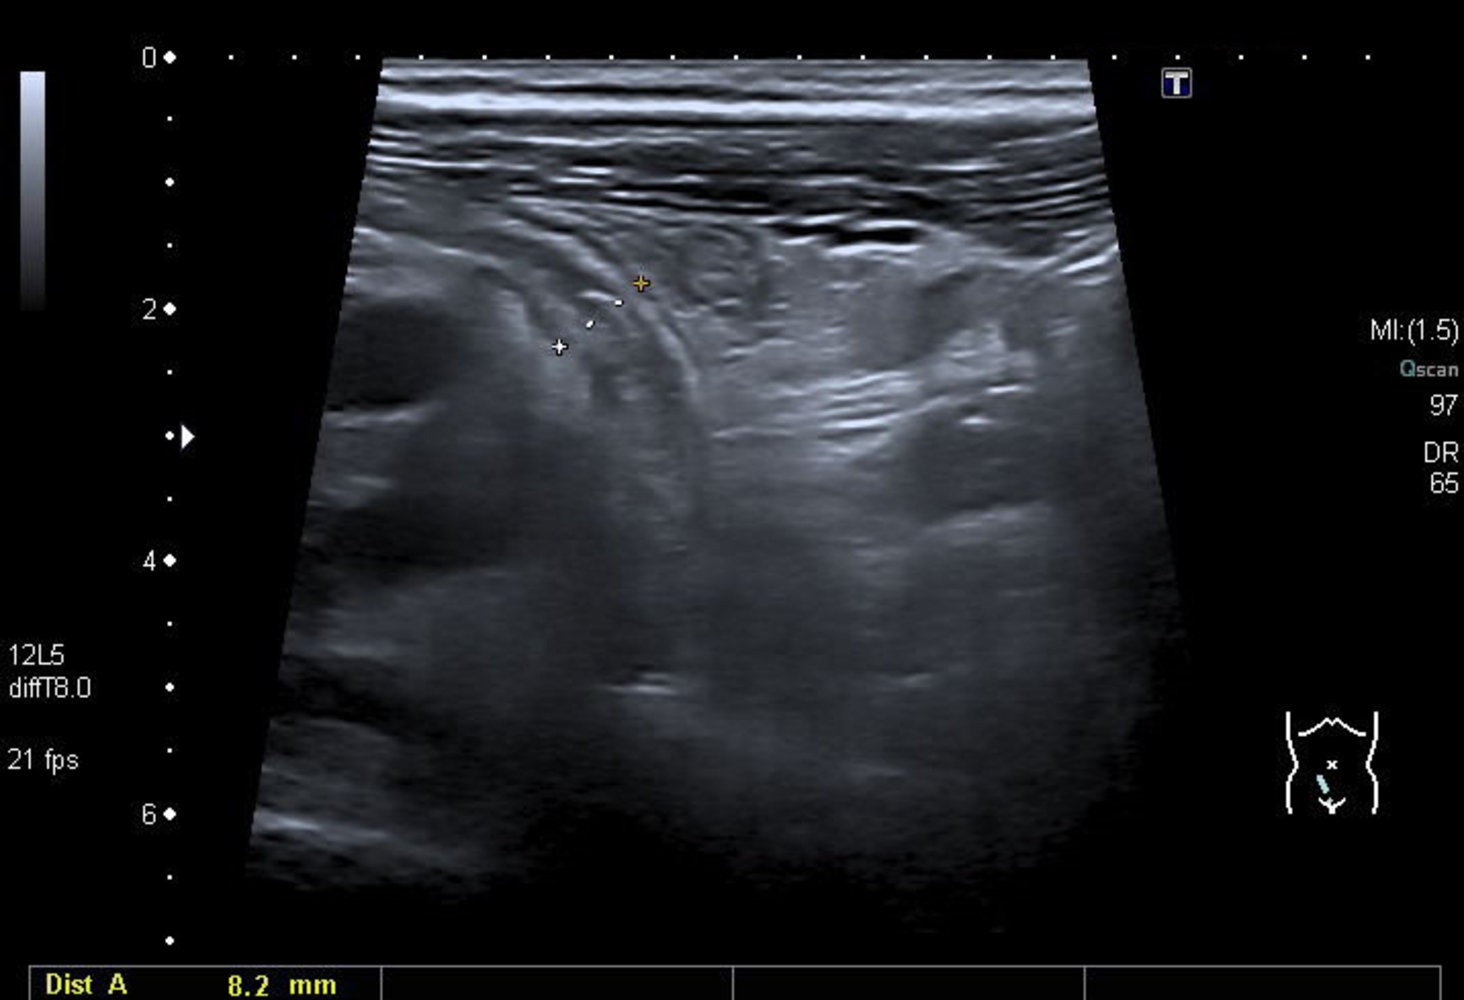

- Ultrasound: First-line in children/pregnancy

- Non-compressible appendix >6 mm, target sign, periappendiceal fluid